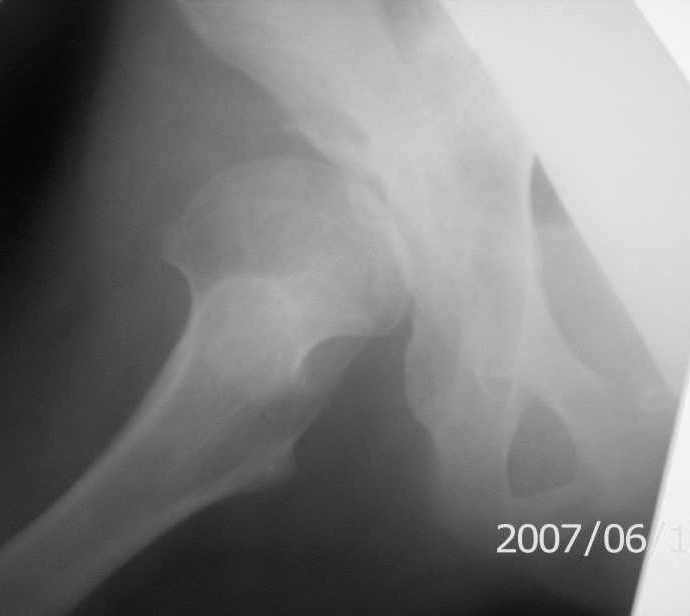

On x-rays coxa magna, shallow true + pseudoacetabulum.Options: salvage

( Shelf /Chiari) or triple osteotomy.Trudno otvetit bez at least basic x-rays.

Ацетабулюм крайне недоразвит. Есть высокий подвывих, можно даже сказать вывих с формированием ложного ацетабулюм. Для головки нет покрытия совсем и расположена она высоко.

На мой взгляд - SHORTENING OSTEOTOMY , VARUS если надо (на основании снимка во внутренней ротации), репозиция головки, CHIARI OSTEOTOMY или SHELF OPERATON Спасибо за интересный случай.